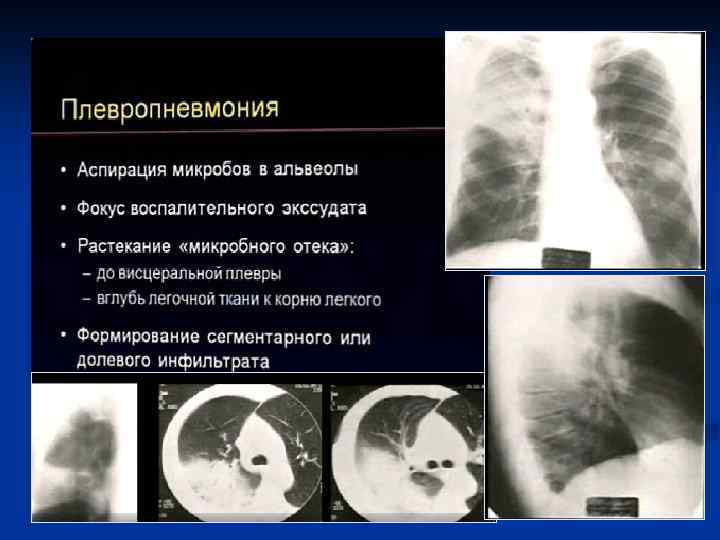

КТ–семиотика плевропневмонии – прямые признаки n n Уплотнение легочной ткани Симптом «воздушной бронхографии» Уменьшение объема Плевральные изменения

Плевропневмония

Округлой формы Отсутствие бронхов в инфильтрате

1 ПН аксиллярного сегмента. Провисание косой междолевой плевры - выпот